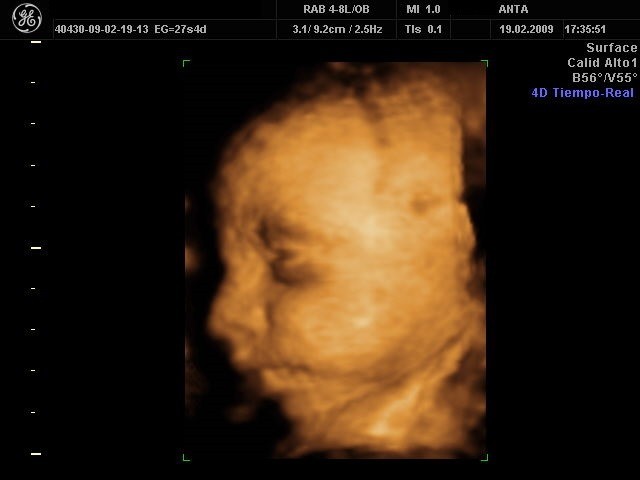

Las ecografías 4D consisten en la obtención de imágenes en 4D por segundo, lo que hace que se pueda visualizar al bebé en volumen y en movimiento a tiempo real. Este tipo de ecografía es muy visual por lo que es una muy buena opción para ver al bebé antes de que nazca. Las mejores ecografías 4Dse obtienen entre las semanas 24 y 30 de embarazo. La proporción de líquido amniótico y el tamaño intermedio del bebé permiten visualizarlo mejor.

En estos casos la ecografía no tiene valor diagnóstico sino que tiene una función lúdica, una solución para satisfacer la curiosidad de los padres que quieren ver a su bebé antes de nacer.